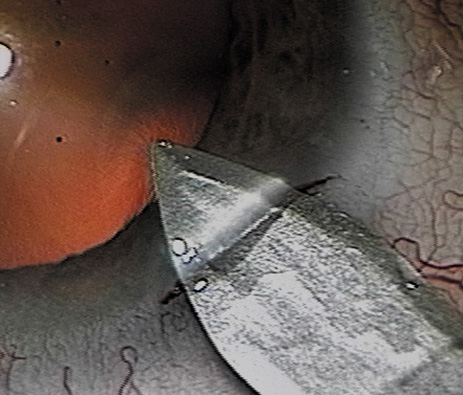

CLEAR CORNEAL AND NEAR-CLEAR CORNEAL INCISIONS

There are several ways to fashion a clear corneal or near-clear corneal incision. The incision can be a single-plane stab into the anterior chamber. However, a two- or three-plane incision may create a more secure wound. The external and internal portions of the incision should be straight lines, tangential to the limbus. Shorter tunnels allow for better visualization and facilitate phacoemulsification handpiece maneuverability, whereas longer “squarer” tunnels have been shown to have higher wound rupture pressures.93 The surgeon must weigh these issues when selecting the tunnel length. Special incisional architectures also work well, including hinged incisions, where the external groove is deeper than the tunnel and trapezoidal incisions.94,95 The authors prefer to make a groove perpendicular to the corneal surface at the most peripheral aspect of cornea, where the incision will just engage limbal vessels. A guarded blade set at 300 to 550 μ works well. Then a keratome is used to tunnel the incision forward within the corneal lamellae before angling the keratome slightly more posteriorly to pierce Descemet's membrane (Fig. 9). Regardless of the technique used to fashion the incision, it is important that the surgeon does not over-manipulate the anterior lip of the incision because such trauma may result in a poorly sealing wound at the end of the case. Also, when inserting an instrument or IOL through the incision, be certain that pressure is directed posteriorly and the incision is of adequate size to avoid stripping Descemet's membrane. Clear corneal incisions are best suited for injectable or foldable IOLs.

Fig. 9. A dual beveled metal keratome (Alconlabs, Ft. Worth, TX) is used to fashion a 3.0-mm near-clear corneal incision.